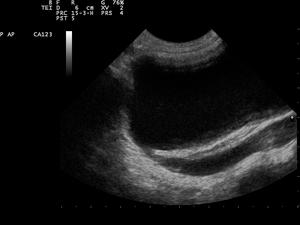

Ultrasound Scan ND 0119092150 0939241.png

Ultrasound image showing abnormal vesicoureteral junction and dilated distal ureter resulting in primary vesicoureteral reflux (VUR).

An abdominal ultrasound might suggest the presence of VUR if ureteral dilatation is present; however, in many circumstances of VUR of low to moderate, even high severity, the sonogram may be completely normal, thus providing insufficient utility as a single diagnostic test in the evaluation of children suspected of having VUR, such as those presenting with prenatal hydronephrosis or urinary tract infection (UTI).[4]